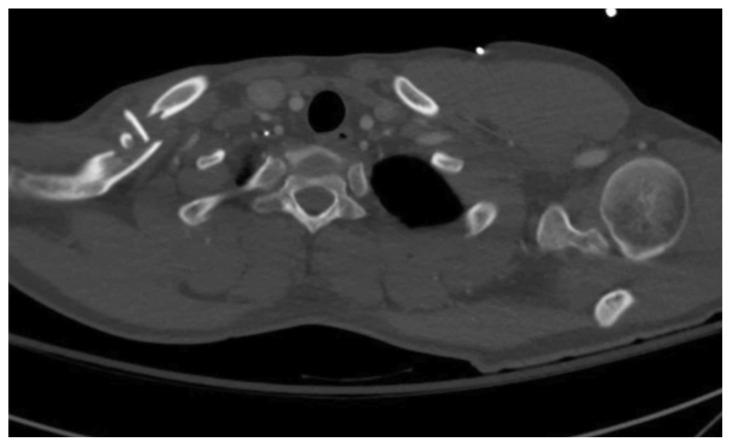

成人锁骨骨折病例报告。

Adult Clavicular Fracture Case Report.

Clavicular fractures make up 2-4% of all fractures. While most are nondisplaced and easily managed, serious complications can arise from more severe fractures. In these cases, immediate surgical intervention is required. However, there lacks a consensus regarding the optimal treatment for fractures that are less severe. Here, we present a case of a 25-year-old male with a comminuted displaced mid-clavicular fracture. This report details the important clinical features of various types of clavicular fractures and discusses the current literature regarding indications for operative and nonoperative management.

锁骨骨折占所有骨折的2% - 4%。虽然大多数骨折无移位且易于处理,但较严重的骨折可能会引发严重并发症。在这些情况下,需要立即进行手术干预。然而,对于不太严重的骨折,目前尚无关于最佳治疗方法的共识。在此,我们报告一例25岁男性的粉碎性移位锁骨中段骨折病例。本报告详细介绍了各类锁骨骨折的重要临床特征,并讨论了当前有关手术和非手术治疗指征的文献。